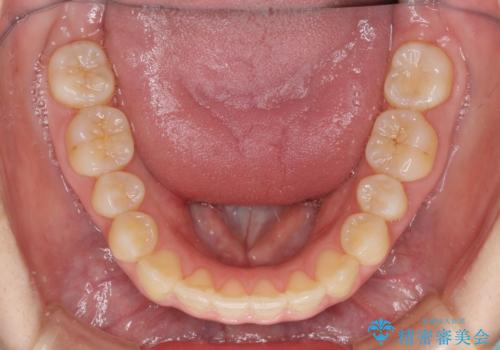

狭い歯列を拡大 拡大装置を併用したインビザライン矯正

八重歯の動きが鈍く、治療期間は長期化しました。

癒着の疑いもありましたが、アンカースクリューを多用し、何とか改善することができました。